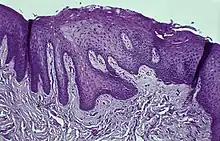

Histology

Immunohistochemical staining with FXIIIa [9] antibody disclosed a population of reactive spindle- or stellate-shaped cells[10] in 11 of 15 cases, located in connective tissue papillae and in a few cases also distributed throughout the lesion. The FXIIIa-stained cells appeared together with the frequently observed stellate, "young" occasionally multinucleated fibroblastic cells observed in more than 50% of patients aged 10–69 years. It is likely that FXIIIA-expressing "mucosal dendrocytes" are pathologically involved in some way.[11][12][13]